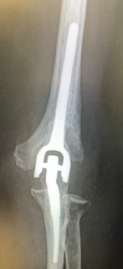

Periprosthetic Humeral Shaft Fracture about Total Elbow Arthroplasties Managed with Medial and Lateral Femoral Strut Allografts and Implant Retention: A Case Report

Elise Ketelaar , Mike McDonald , James Dietz

………………………………p.240-244